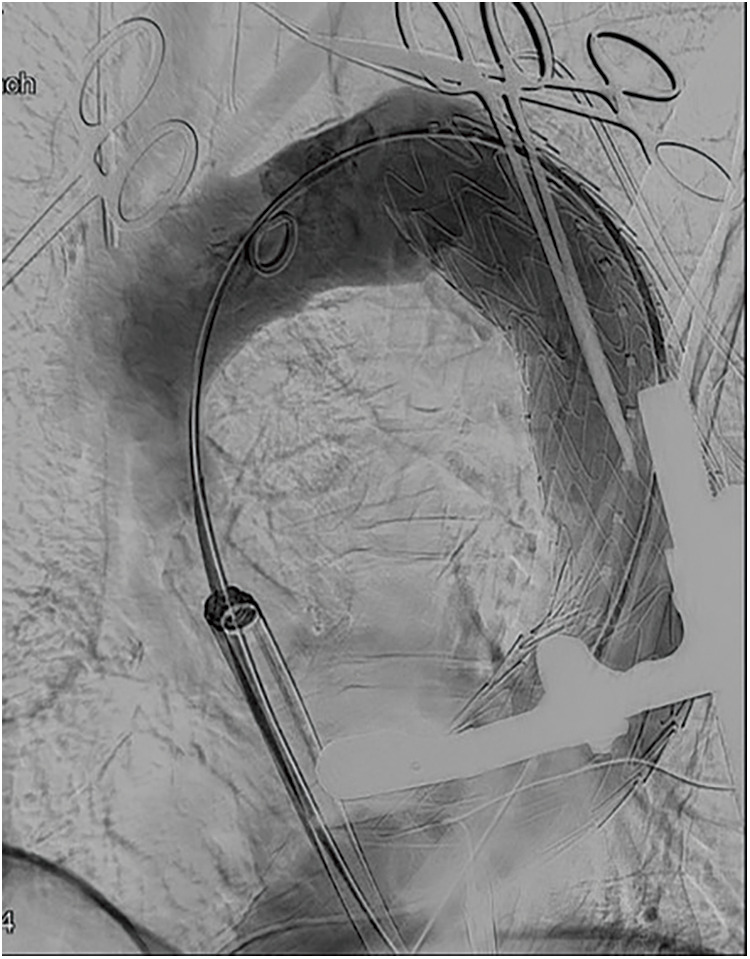

胸主动脉瘤(TAAs)的胸腔内血管主动脉修复术(TEVAR)是高风险患者的另一种治疗选择。虽然传统上是通过经胸途径进行,但有时由于入路不畅而难以实施。我们报告了一例 90 岁男性患者的病例,他在接受食道癌计算机断层扫描时意外被诊断出患有降支 TAA。患者曾接受过两次 Y 型移植物置换术。他的 Y 型移植物腿角度很大,因此经股动脉入路被认为是困难的。因此,患者接受了经心尖 TEVAR 手术。术后恢复顺利。经心尖 TEVAR 是治疗超高龄患者入路不畅的 TAAs 的有效方法。

Thoracic endovascular aortic repair (TEVAR) for thoracic aortic aneurysms (TAAs) is an alternative treatment option for high-risk patients. While conventionally performed via a transfemoral approach, it is sometimes difficult due to poor access routes. We report the case of a 90-year-old man who was incidentally diagnosed with a descending TAA while undergoing computed tomography for esophageal cancer. The patient had undergone Y-graft replacement twice. His Y-graft leg was highly angulated; therefore, a transfemoral approach was considered difficult. Consequently, transapical TEVAR was performed. The postoperative course was uneventful. Transapical TEVAR can be a useful treatment option for TAAs with poor access routes in super-old patients.